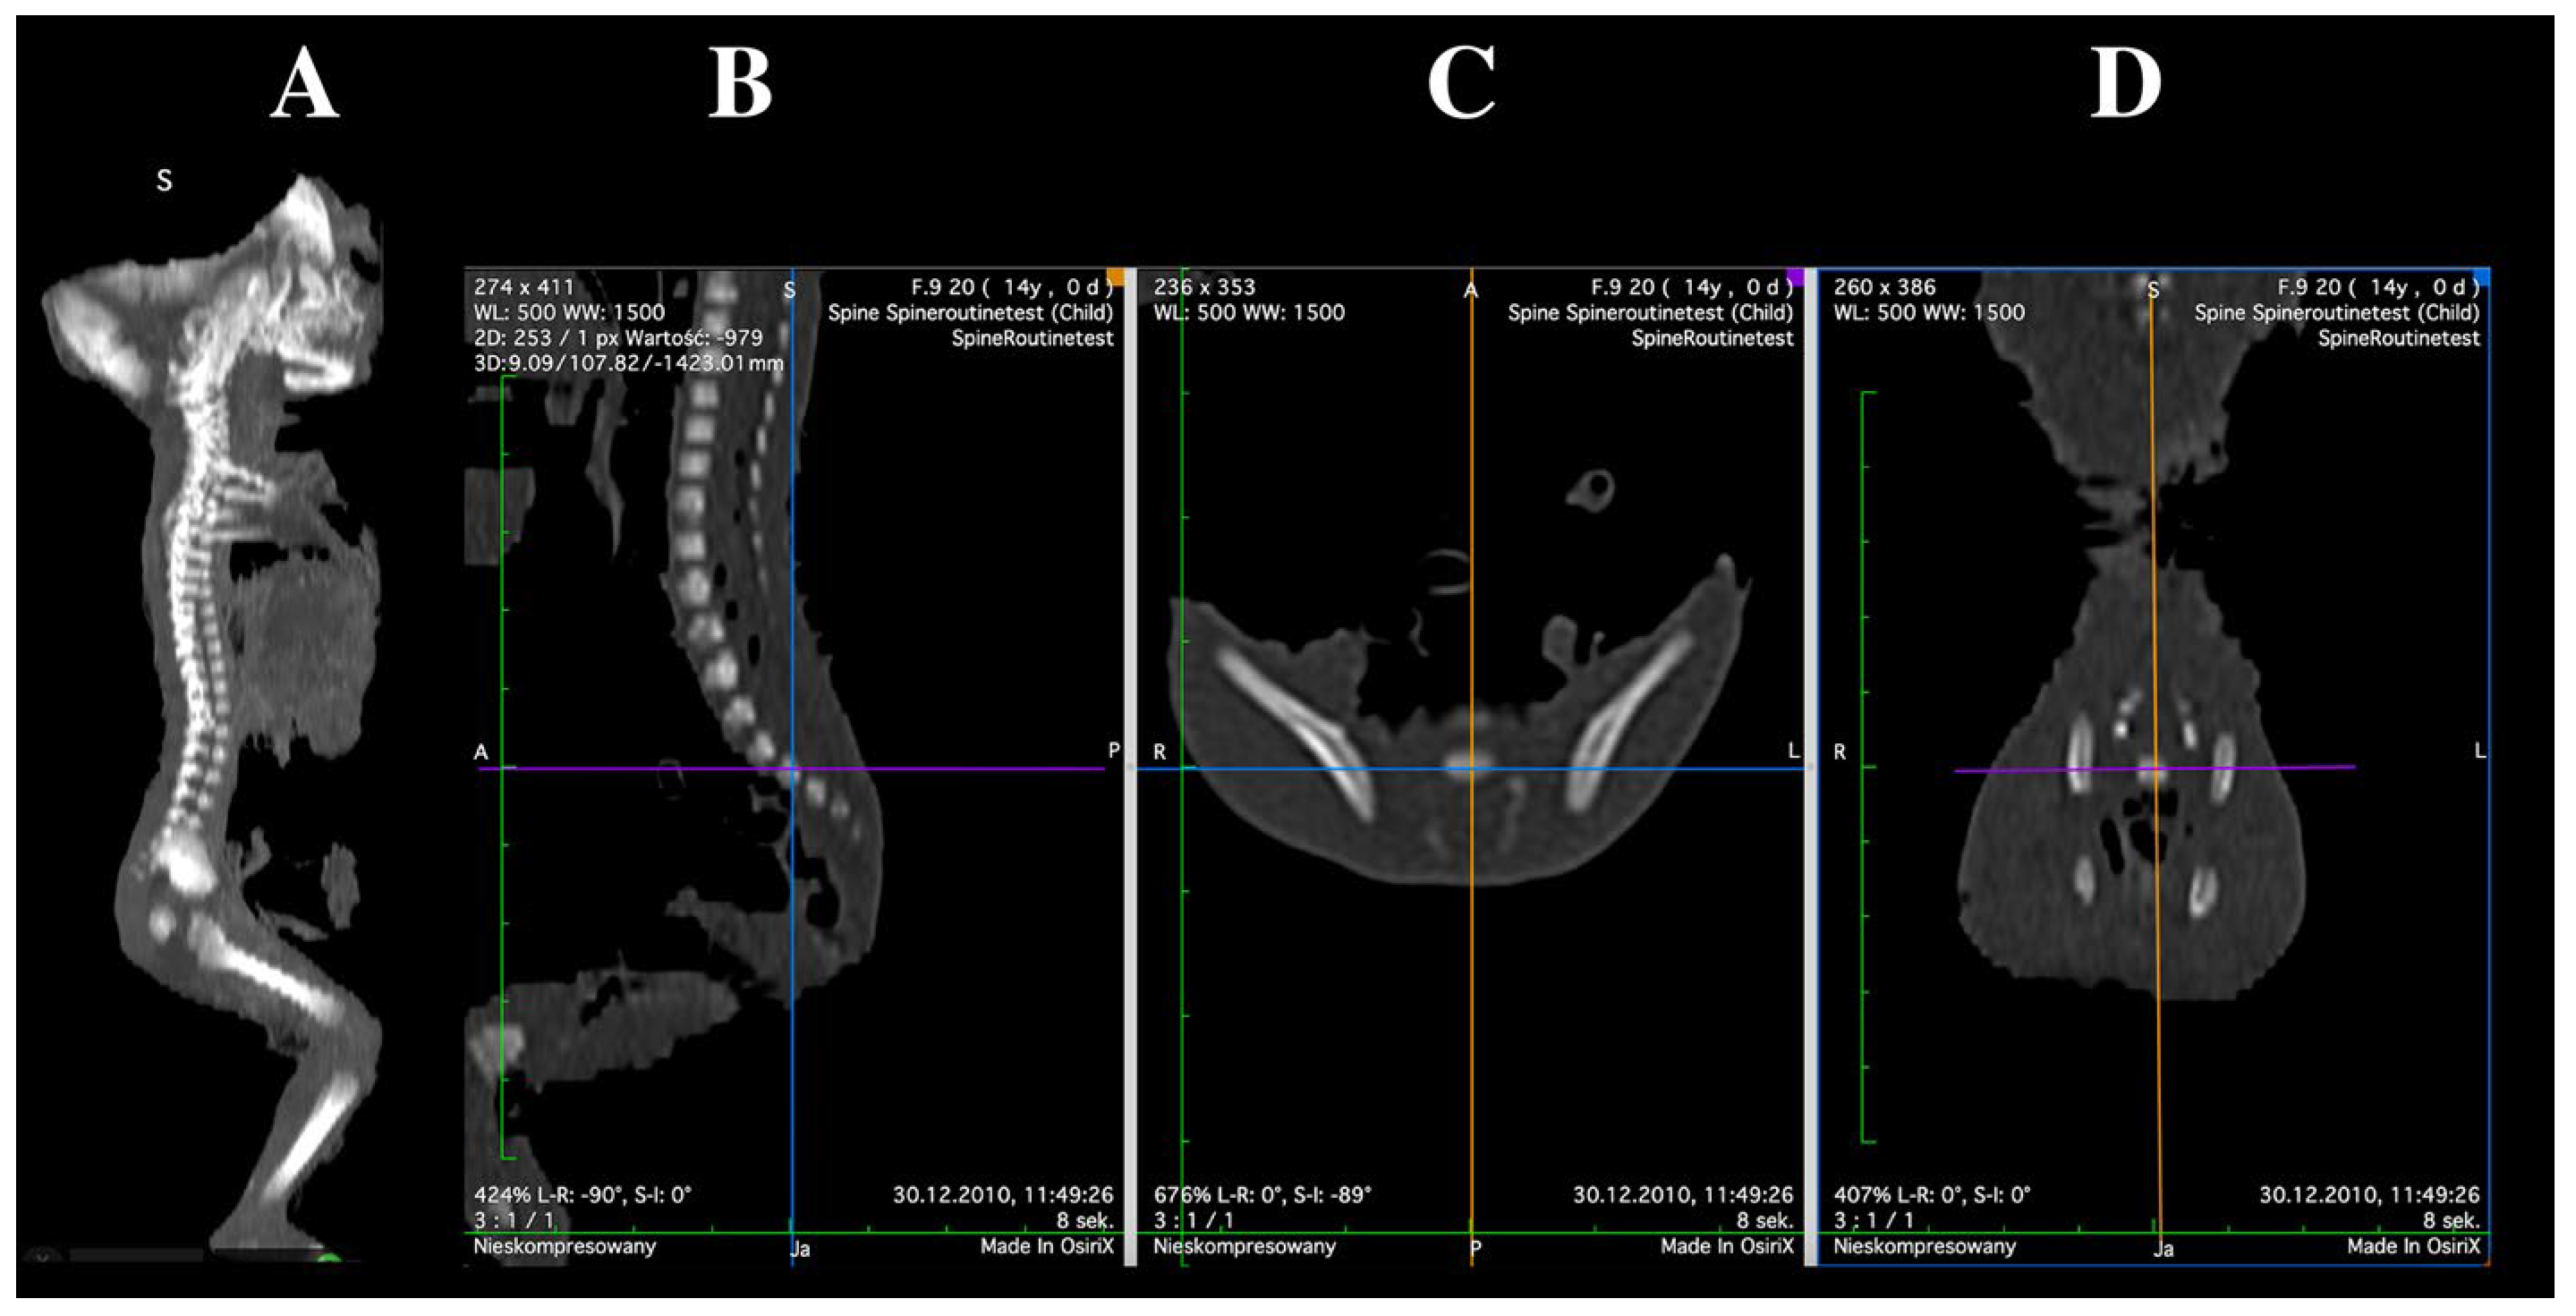

2.2. Morphometric Measurements

- Vertebral body height—the maximum distance between the superior and inferior borders of the vertebral body in the sagittal plane;

- Transverse diameter of vertebral body—the maximum distance between the lateral edges of the vertebral body in the transverse plane;

- Transverse diameter of body ossification center—the maximum distance between the lateral edges of the ossification center in the transverse plane;

- Sagittal diameter of vertebral body—the maximum distance between the anterior and posterior borders of the vertebral body in the sagittal plane;

- Sagittal diameter of body ossification center—the maximum distance between the anterior and posterior borders of the ossification center in the sagittal plane;

- Cross-sectional area of vertebral body—the area determined based on the contour of the vertebral body in the transverse plane;

- Cross-sectional area of body ossification center—the area determined based on the contour of the ossification center in the transverse plane;

- Volume of the ossification center—calculated using three-dimensional reconstruction software(OsiriX MD 3.9), taking into account spatial orientation and X-ray attenuation properties of the mineralizing tissue.